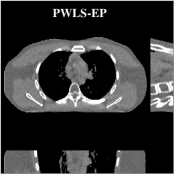

Fig.Β 5 shows the reconstructions and the corresponding error (magnitudes) images (shown for the central axial, sagittal, and coronal planes) for FDK, PWLS-EP, and PWLS-ULTRA () with the patch-based weights. Compared to FDK and PWLS-EP, PWLS-ULTRA significantly improves image quality by reducing noise and preserving structural details (see zoom-ins). Fig.Β 6 shows the RMSE for each axial slice in the PWLS-EP and PWLS-ULTRA (with the weights ) reconstructions. PWLS-ULTRA clearly provides large improvements in RMSE for many slices, with greater improvements near the central slice.

Fig.Β 7 shows the reconstructions (shown for the central axial plane in the 3D volume) for FDK (provided by GE Healthcare), PWLS-EP (corresponds to Fig.Β 8(a)), and PWLS-ULTRA with (corresponds to Fig.Β 9(a)). The PWLS-ULTRA reconstruction has lower artifacts and noise. Moreover, the image features and edges are better reconstructed by PWLS-ULTRA than by PWLS-EP or FDK.